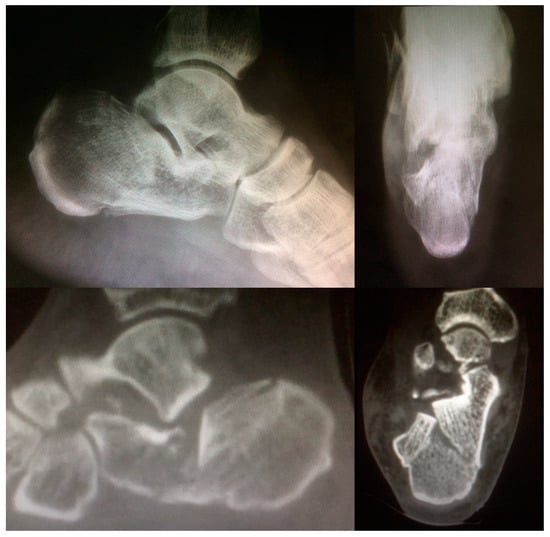

2.2. Surgical Procedure

- Janzen, D.L.; Connell, D.G.; Munk, P.L.; Buckley, R.E.; Meek, R.N.; Schechter, M.T. Intraarticular fractures of the calcaneus: Value of CT findings in determining prognosis. AJR Am. J. Roentgenol. 1992, 158, 1271–1274. [Google Scholar] [CrossRef]

| Patient Position | Lateral Decubitus |

| Intra-operatory aids | C-arm fluoroscopy |

| Anatomical markers | Tip of the lateral malleolus Base of the 4th metatarsal bone |

| Fragments exposure | Release of the inferior peroneal retinaculum Release of the CFL and subtalar ligaments SJ exposure |

| Steps for fragments reduction | Reduction of the PT fragment to the sustentacular constant fragment Reduction of articular fragments from posterior to anterior |